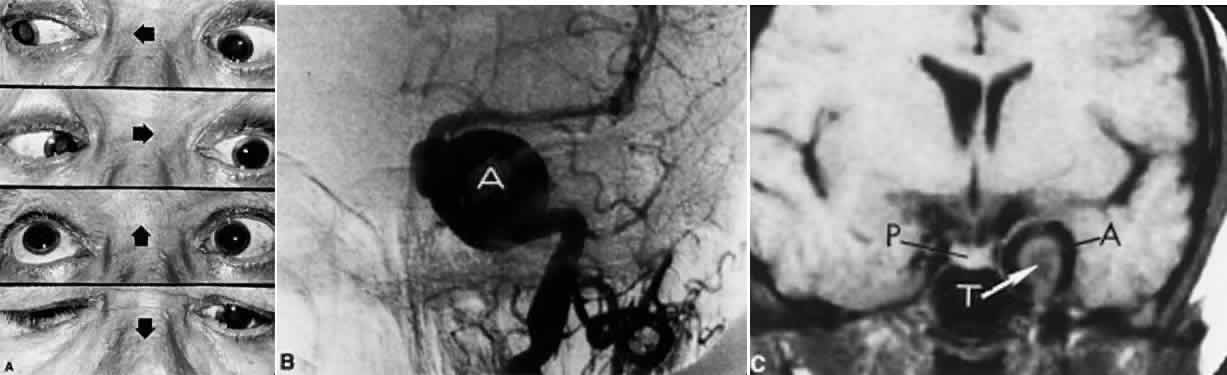

Oculomotor synkinesis is frequently observed in congenital third nerve palsies.39,120–122 The spontaneous and progressive development of oculomotor synkinesis in patients with no prior acute oculomotor palsy111,114–117 is seen most commonly with slowly growing lesions in the cavernous sinus, usually meningiomas or aneurysms, and has been termed primary oculomotor synkinesis. Varma and Miller123 pointed out that although aneurysms typically present with acute, painful oculomotor pareses, they may produce painless third nerve palsies with primary aberrant regeneration. Secondary oculomotor synkinesis, that is, synkinesis following recognized acquired oculomotor palsy, most commonly occurs in association with trauma or aneurysms, but may rarely be seen with neoplasia or even ophthalmoplegic migraine.124 Misdirection has not been documented after ischemic (diabetic) ophthalmoplegia or demyelinative syndromes.

After acute ophthalmoplegia, clinical signs of dyskinesia begin at about 8 to 10 weeks, accompanying variable degrees of recovered function (Fig. 15). When recovery begins earlier, synkinesia is less frequent—and, of course, when there is no recovery, there is no synkinesia. Several paradoxic patterns may evolve: elevation of the upper lid on attempted use of the inferior (pseudo-von Graefe sign) or medial rectus muscles (“reverse Duane” syndrome) (see Fig. 13); adduction or retraction of the globe on attempted downward or upward gaze; and a light-near (or lateral gaze) pupillary dissociation with constriction of a larger than normal pupil occurring on attempted adduction. According to Hepler and Cantu,118 of 25 patients with aberrant oculomotor regeneration after posterior communicating artery aneurysms, 20 demonstrated the pseudo-von Graefe phenomenon of lid elevation on attempted downgaze. This critical sign is best appreciated by directing the patient's gaze first downward, and then slowly from side to side. Czarnecki and Thompson119 reported other pupillary anomalies, including asynchronous sectoral contractions with both light stimulation and eye movement.

Fig. 15. Aberrant regeneration of left oculomotor nerve following head trauma. Note modest limitation of medial rectus function and marked deficit of superior rectus. On attempted downward gaze (inferior rectus) the left lid elevates, that is, the pseudo-Graefe phenomenon.